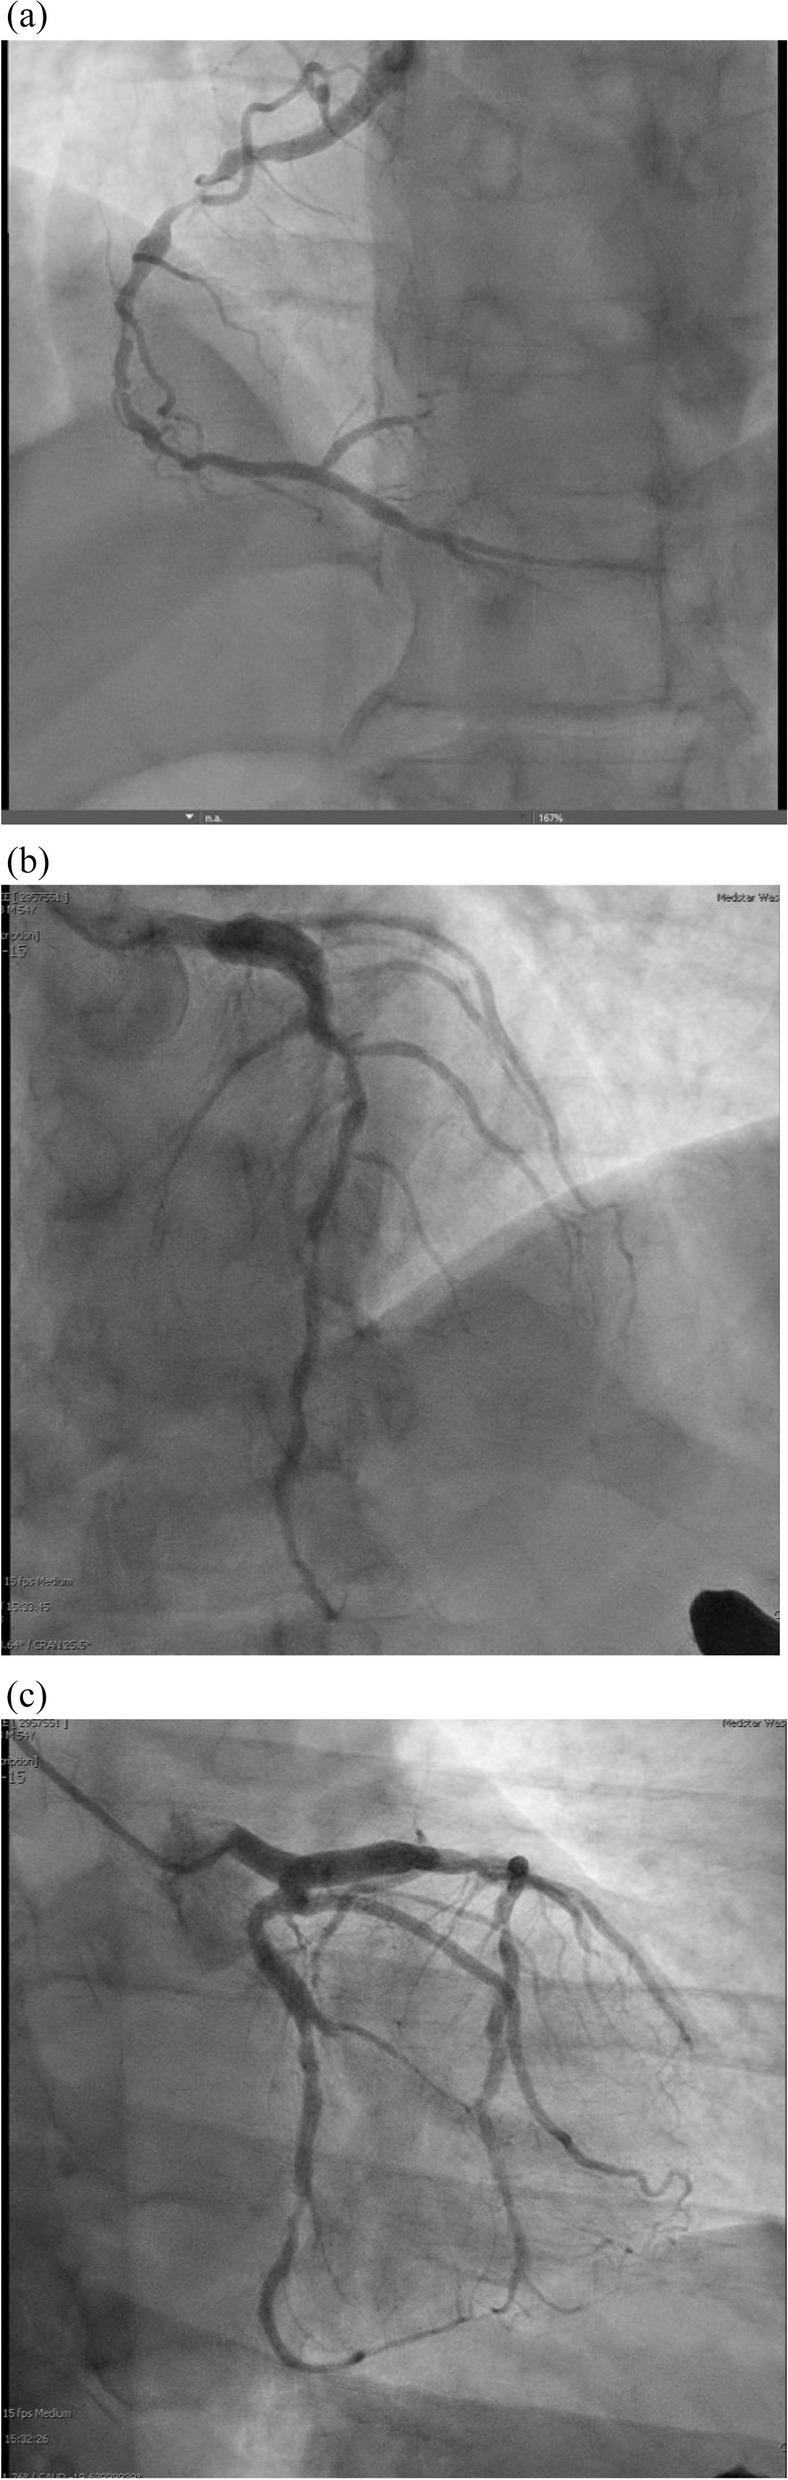

冠状动脉受累的严重程度难以通过实验室监测来评估,但冠状动脉疾病与几种临床症状相关。弗雷明汉危险因素不能充分估计疾病负担。要将动脉粥样硬化与动脉炎分开,需要先进的血管造影方法。治疗包括抗凝、免疫抑制和血运重建。经皮冠状动脉介入治疗(PCI)一直是主要的治疗方法,尽管支架置入后由于管腔直径的不规则变化和新生内膜形成的报告,支架的应用受到限制。

当移植物选择避开 SV 的血管区域时,冠状动脉旁路移植术(CABG)提供了明确的治疗方法。除了回顾、更新和讨论文献外,我们还报告了一种新型的 CABG 构型。越来越多的证据表明,特定的临床症状提示存在冠状动脉受累。